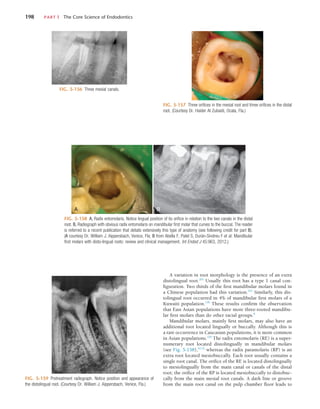

odontic explorer can be used to probe the depth of the access,

using magnification or the DOM. Often a small opening into

the chamber is present, or the dentin is very thin and the

explorer penetrates into the chamber. The depth and angle of

penetration should be assessed for any deviation away from the

long axis of the root in both the mesiodistal and buccolingual

dimensions, and the penetration angle should be realigned if